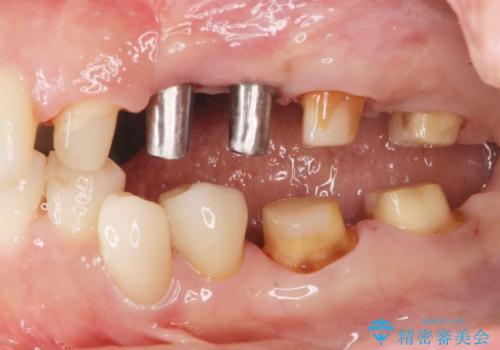

- 「長年使ってきた銀歯からなんとなく臭いがするので治したい、今後しっかり噛めるような歯の治療を受けたい。」

と希望され来院されました。

銀歯を除去したのち、虫歯を丁寧に除去し、歯を残せるのかどうかをしっかりと評価し、長期的な予後を見据えた虫歯治療を行っていきます。

銀歯の下で虫歯が再発していた歯は、無理に残しても割れてしまう可能性が非常に高いと考えたため、相談の上抜去を行いインプラント治療を行っていくこととしました。